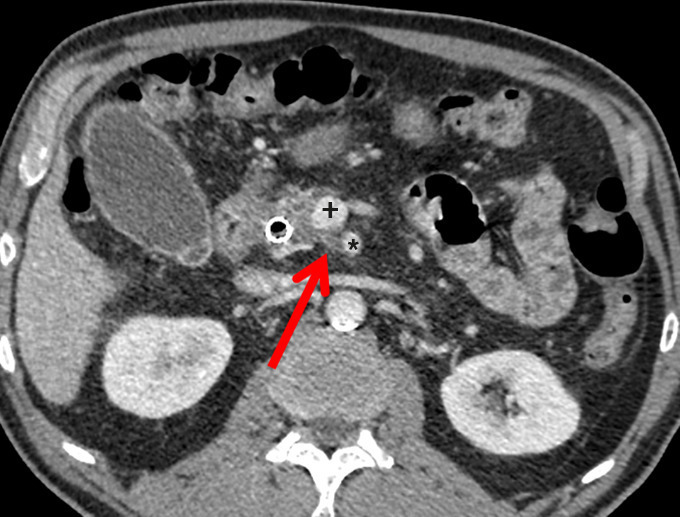

Il a pour but l’exérèse complète d’une tumeur localisée, avec des marges supérieures à 1 mm (résection R0). La survie médiane est alors de 30-40 mois. La plus importante au plan pronostique est la marge rétrovasculaire, ou lame rétroporte (tissu graisseux, lymphatique et nerveux, située en arrière de la VMS et la VP et au contact de l’AMS ; fig. 1A).

Évaluer la résécabilité secondaire d’une tumeur borderline après CT  RCT peut être difficile et repose sur un faisceau d’arguments cliniques (disparition des douleurs cœliaques, reprise de poids), biologiques (baisse du CA 19-9 sérique) et radiologiques (réduction même partielle du contact tumeur-axe vasculaire, diminution même modérée du diamètre tumoral ; fig. 1B). Après traitement d’induction, on propose une exérèse s’il n’y a pas de progression en TDM et si le taux de CA 19-9 sérique reste bas ou diminue nettement (< 50 %).